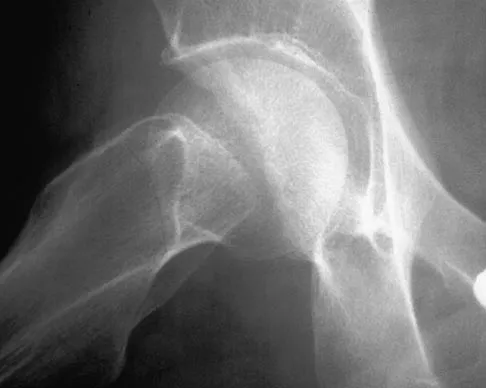

Figures 22a and 22b show the radiographs of a patient who reports stiffness of the hip and associated pain. Management should consist of

The patient has grade IV heterotopic ossification with the limb in an abnormal nonfunctional position. Treatment should consist of excision of the bone to restore hip motion and prophylaxis to prevent recurrent formation. The best time to excise the bone is controversial, with no conclusive evidence supporting early or late excision. Pellegrini VD Jr, Koniski AA, Gastel JA, Rubin P, Evarts CM: Prevention of heterotopic ossification with irradiation after total hip arthroplasty: Radiation therapy with a single dose of eight hundred centigray administered to a limited field. J Bone Joint Surg Am 1992;74:186-200.